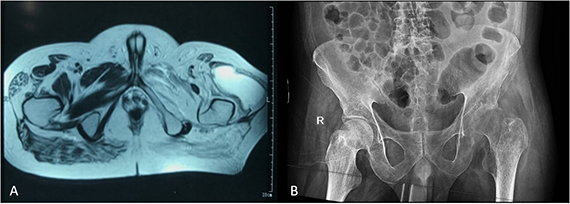

En la Figura 2 A la Resonancia magnética (RM) de pelvis al ingreso donde se evidencia un absceso en zona lateral a cabeza de fémur izquierdo. En la Figura 2 B la radiografía de pelvis al mes del tratamiento donde se aprecia erosiones subcondrales a nivel de la cabeza del fémur izquierdo, severa disminución del espacio coxofemoral y extenso patrón permeativo mal definido a nivel de la diáfisis que incluye la línea intertrocantérea.

Sobre la TBCOA, la RM evidencia coexistencia granular y exudativa, pero el absceso indica predominancia del último (Figura 2 A), por otro lado, el patrón permeativo de la radiografía (Figura 2 B) determina la evolución en la destrucción de la cabeza del fémur.